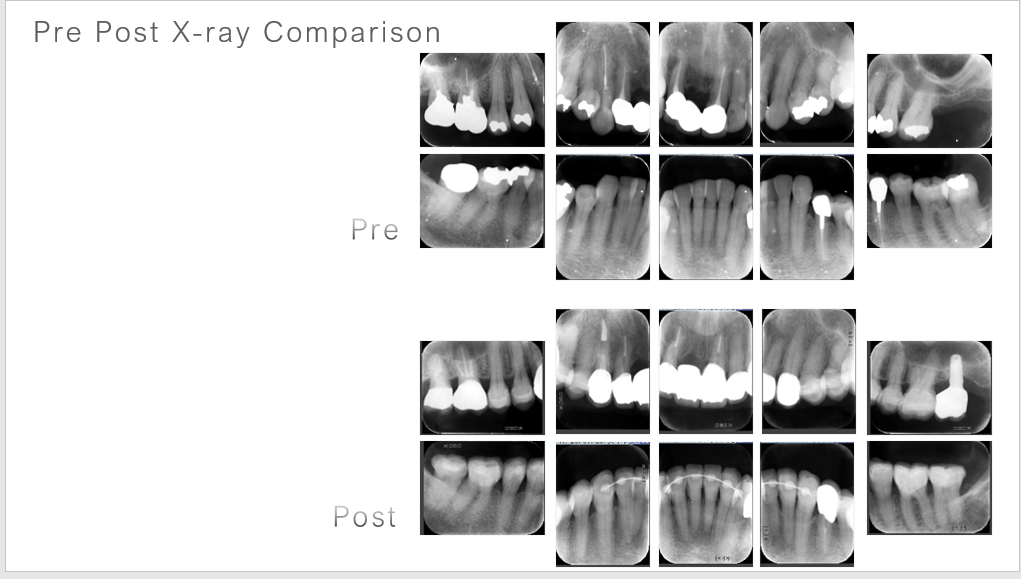

術前、術後の比較です。

この型取りとレントゲンが証拠になります。エナメル質を残しています。

矯正治療が効いています。